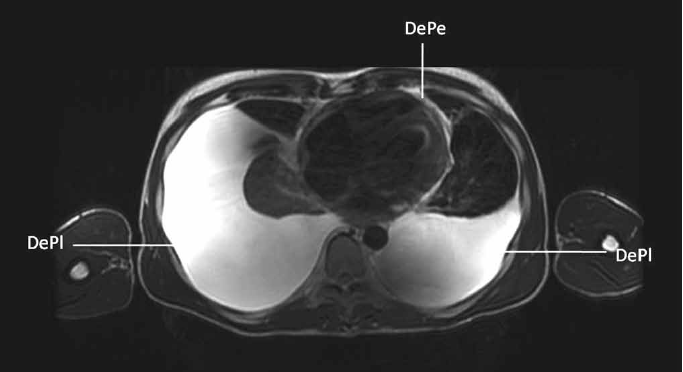

El ecocardiograma reveló insuficiencia mitral grave y pericardio engrosado con reducción del deslizamiento entre sus hojas, con variación respiratoria superior al 25% del flujo mitral, lo que indicó restricción. La tomografía computada mostró derrame pericárdico (Figura 2). A pesar del PPD negativo, la principal sospecha diagnóstica fue una PC causada por TB y, de esta forma, se inició un esquema con rifampicina, isoniazida, pirazinamida y etambutol (RIPE). Este esquema fue suspendido al séptimo día debido a la aparición de ictericia. La búsqueda de BAAR (bacilos acidorresistentes) y el cultivo para el BK en el líquido pleural fueron negativos. Se discutió la posibilidad de la realización de una pericardiectomía, debido al patrón restrictivo, pero no fue realizada, pues hubo un empeoramiento importante del cuadro clínico, con el agravamiento del derrame pleural bilateral según lo demostrado por la resonancia magnética nuclear (Figura 3). Se decidió entonces por el reinicio escalonado del esquema RIPE y mantenimiento de la terapia con corticoides. El paciente no presentó efectos adversos y evolucionó con una mejora progresiva del cuadro clínico. Los signos de restricción desaparecieron en los exámenes ecocardiográficos seriados después de la introducción del esquema RIPE y corticoterapia. Recibió alta hospitalaria después de cuatro meses de internación.

Figura 3. Resonancia magnética nuclear de tórax que muestra el derrame pleural bilateral (DePl) y el derrame pericárdico (DePe).